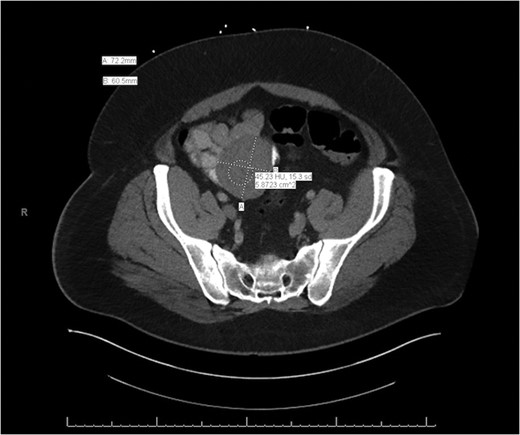

General surgery was then consulted for further recommendations. A CT of the abdomen and pelvis with contrast was performed and demonstrated a 7.2 × 6.8 × 6.1 cm3 lesion arising from the mid-to-distal small bowel loop with no evidence of significant enhancement. It appeared mobile within the mesentery of the small bowel when compared to previous imaging (Figs. 1 and 2). The patient had continued to bleed and required transfusion with five units of packed red blood cells; therefore, it was decided to take the patient to the operating room for a diagnostic laparoscopy.

Axial slice of the CT of the abdomen/pelvis demonstrating a lesion arising from the mid-to-distal small bowel.